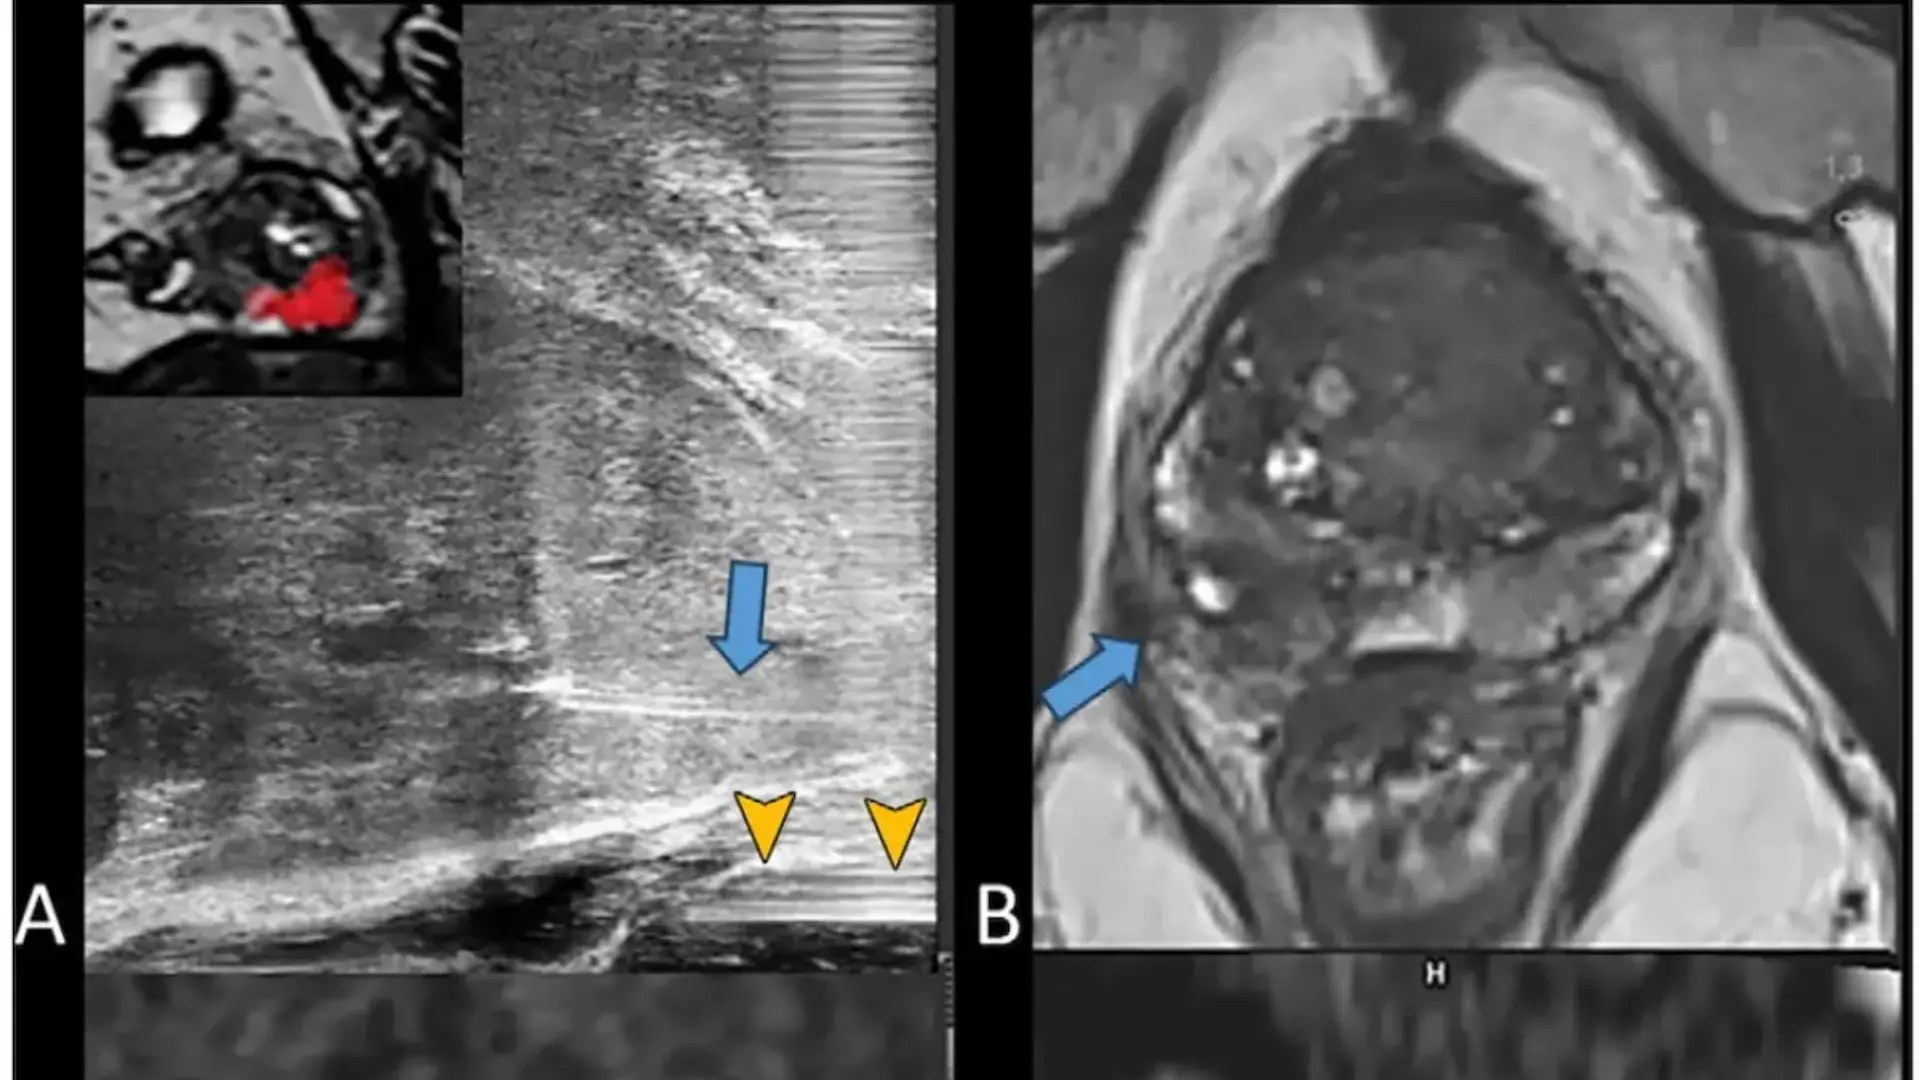

La micro-ecografía, operando a 29 MHz, ofrece una resolución de 70 μm, triplicando la capacidad de los equipos transrectales convencionales.

Esta alta resolución permite identificar con exactitud hasta el 91% de los focos tumorales previamente detectados en la MRI. La fusión de imágenes durante la fase de planificación posibilita ajustar la posición de la aguja de ablación, garantizando una cobertura óptima del volumen tumoral.

Se utilizó MRI para planificar el procedimiento y fusionar imágenes, permitiendo ajustar la posición de la aguja y asegurar la cobertura del volumen tumoral. La micro-ecografía, gracias a su alta resolución, facilitó la localización precisa de los focos cancerígenos, alcanzando una tasa de detección del 91 por ciento.